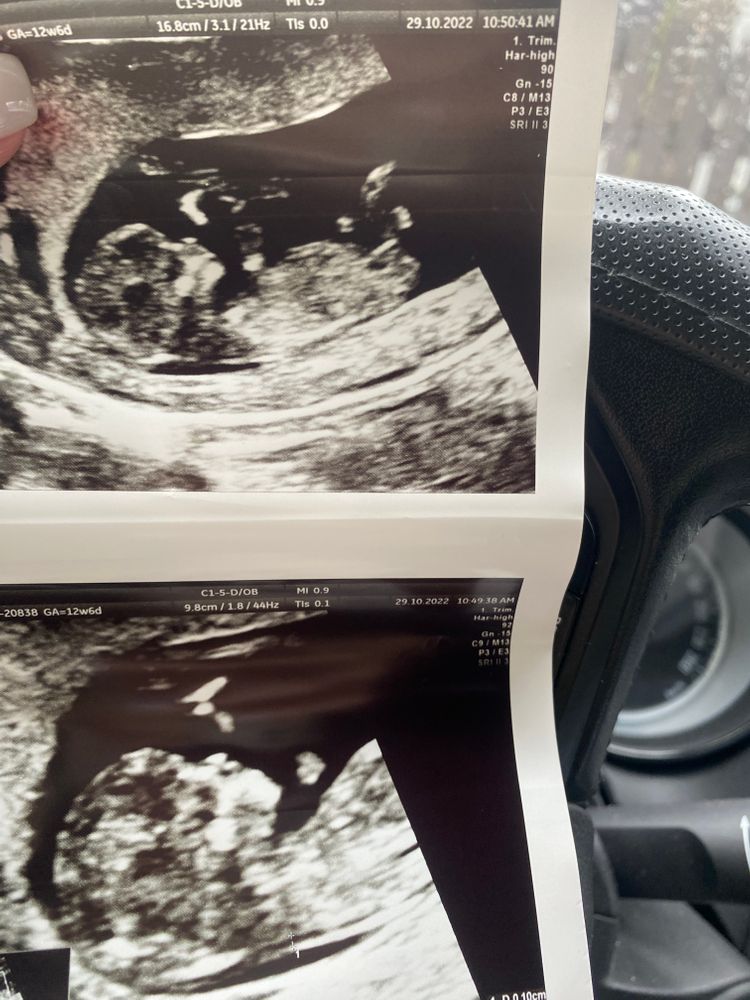

Нам в 13 недель предположили мальчика) были платно на 1 скрининге, все очень подробно рассматривали прицепляю наши фото Изображение Изображение

30.10.2022

Anastasia, а у вашего малыша не совсем понятно, но больше на мальчика.

Аня, я бы сказала что у вас девочка на 98%, бугорок прям хорошо видно

Мальчик?

Anastasia, я вижу небольшой градус подъёма, просто на узи под разными углами смотрят и видно лучше поднят бугорок или нет) У моего сына на узи в 13 недель бугорок прямо наверх уже торчал, там было все понятно, а в 11+4 недель было как у Вас)